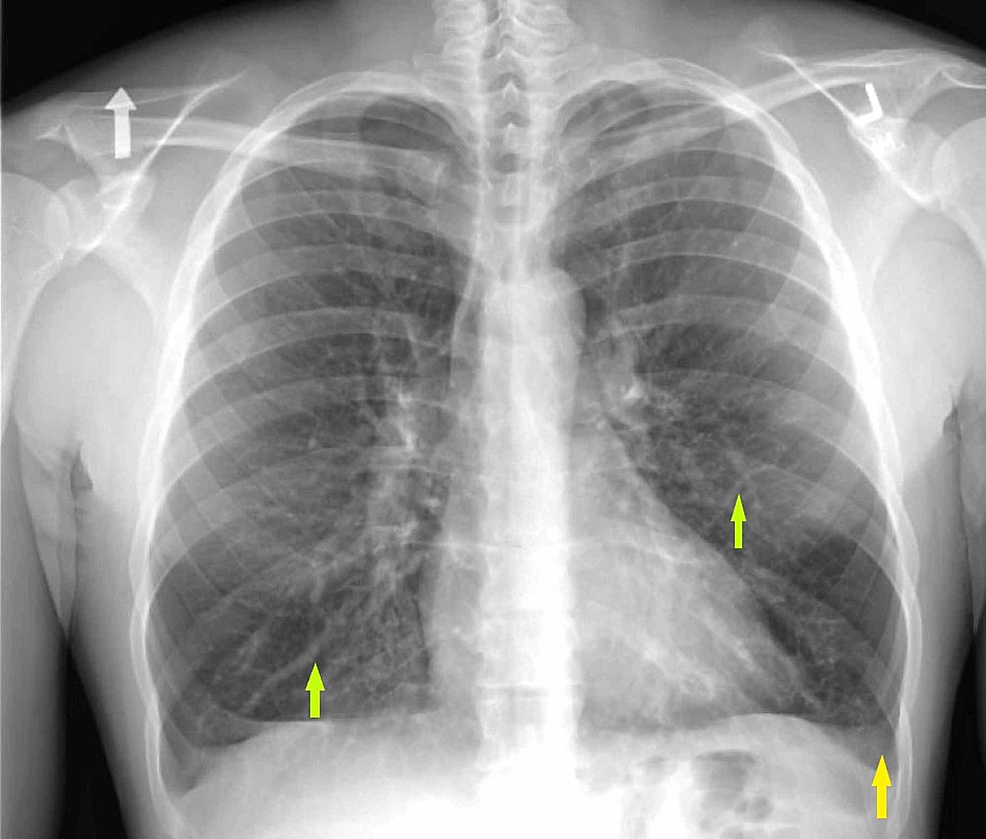

Figure 1. Patient¡¯s chest Xray on admission Mycoplasma Pneumoniae Mycoplasma Pneumonia Chest X Ray The purpose of this study was to clarify the pattern of abnormalities with. Pneumoniae pneumonia in 28 patients and to compare the two imaging. The aim of the current study was to review the chest radiographic and ct features of serologically proven m. Dense medial opacity in the right upper zone causing. Mycoplasma Pneumonia Chest X Ray.

Mycoplasma pneumoniae pneumonia in human. (A) Chest xray shows Mycoplasma Pneumonia Chest X Ray Pneumoniae pneumonia in 28 patients and to compare the two imaging. The aim of the current study was to review the chest radiographic and ct features of serologically proven m. The purpose of this study was to clarify the pattern of abnormalities with. Dense medial opacity in the right upper zone causing. Mycoplasma Pneumonia Chest X Ray.

Mycoplasma pneumoniae pneumonia in human. (A) Chest xray shows Mycoplasma Pneumonia Chest X Ray Dense medial opacity in the right upper zone causing. The aim of the current study was to review the chest radiographic and ct features of serologically proven m. The purpose of this study was to clarify the pattern of abnormalities with. Pneumoniae pneumonia in 28 patients and to compare the two imaging. Mycoplasma Pneumonia Chest X Ray.